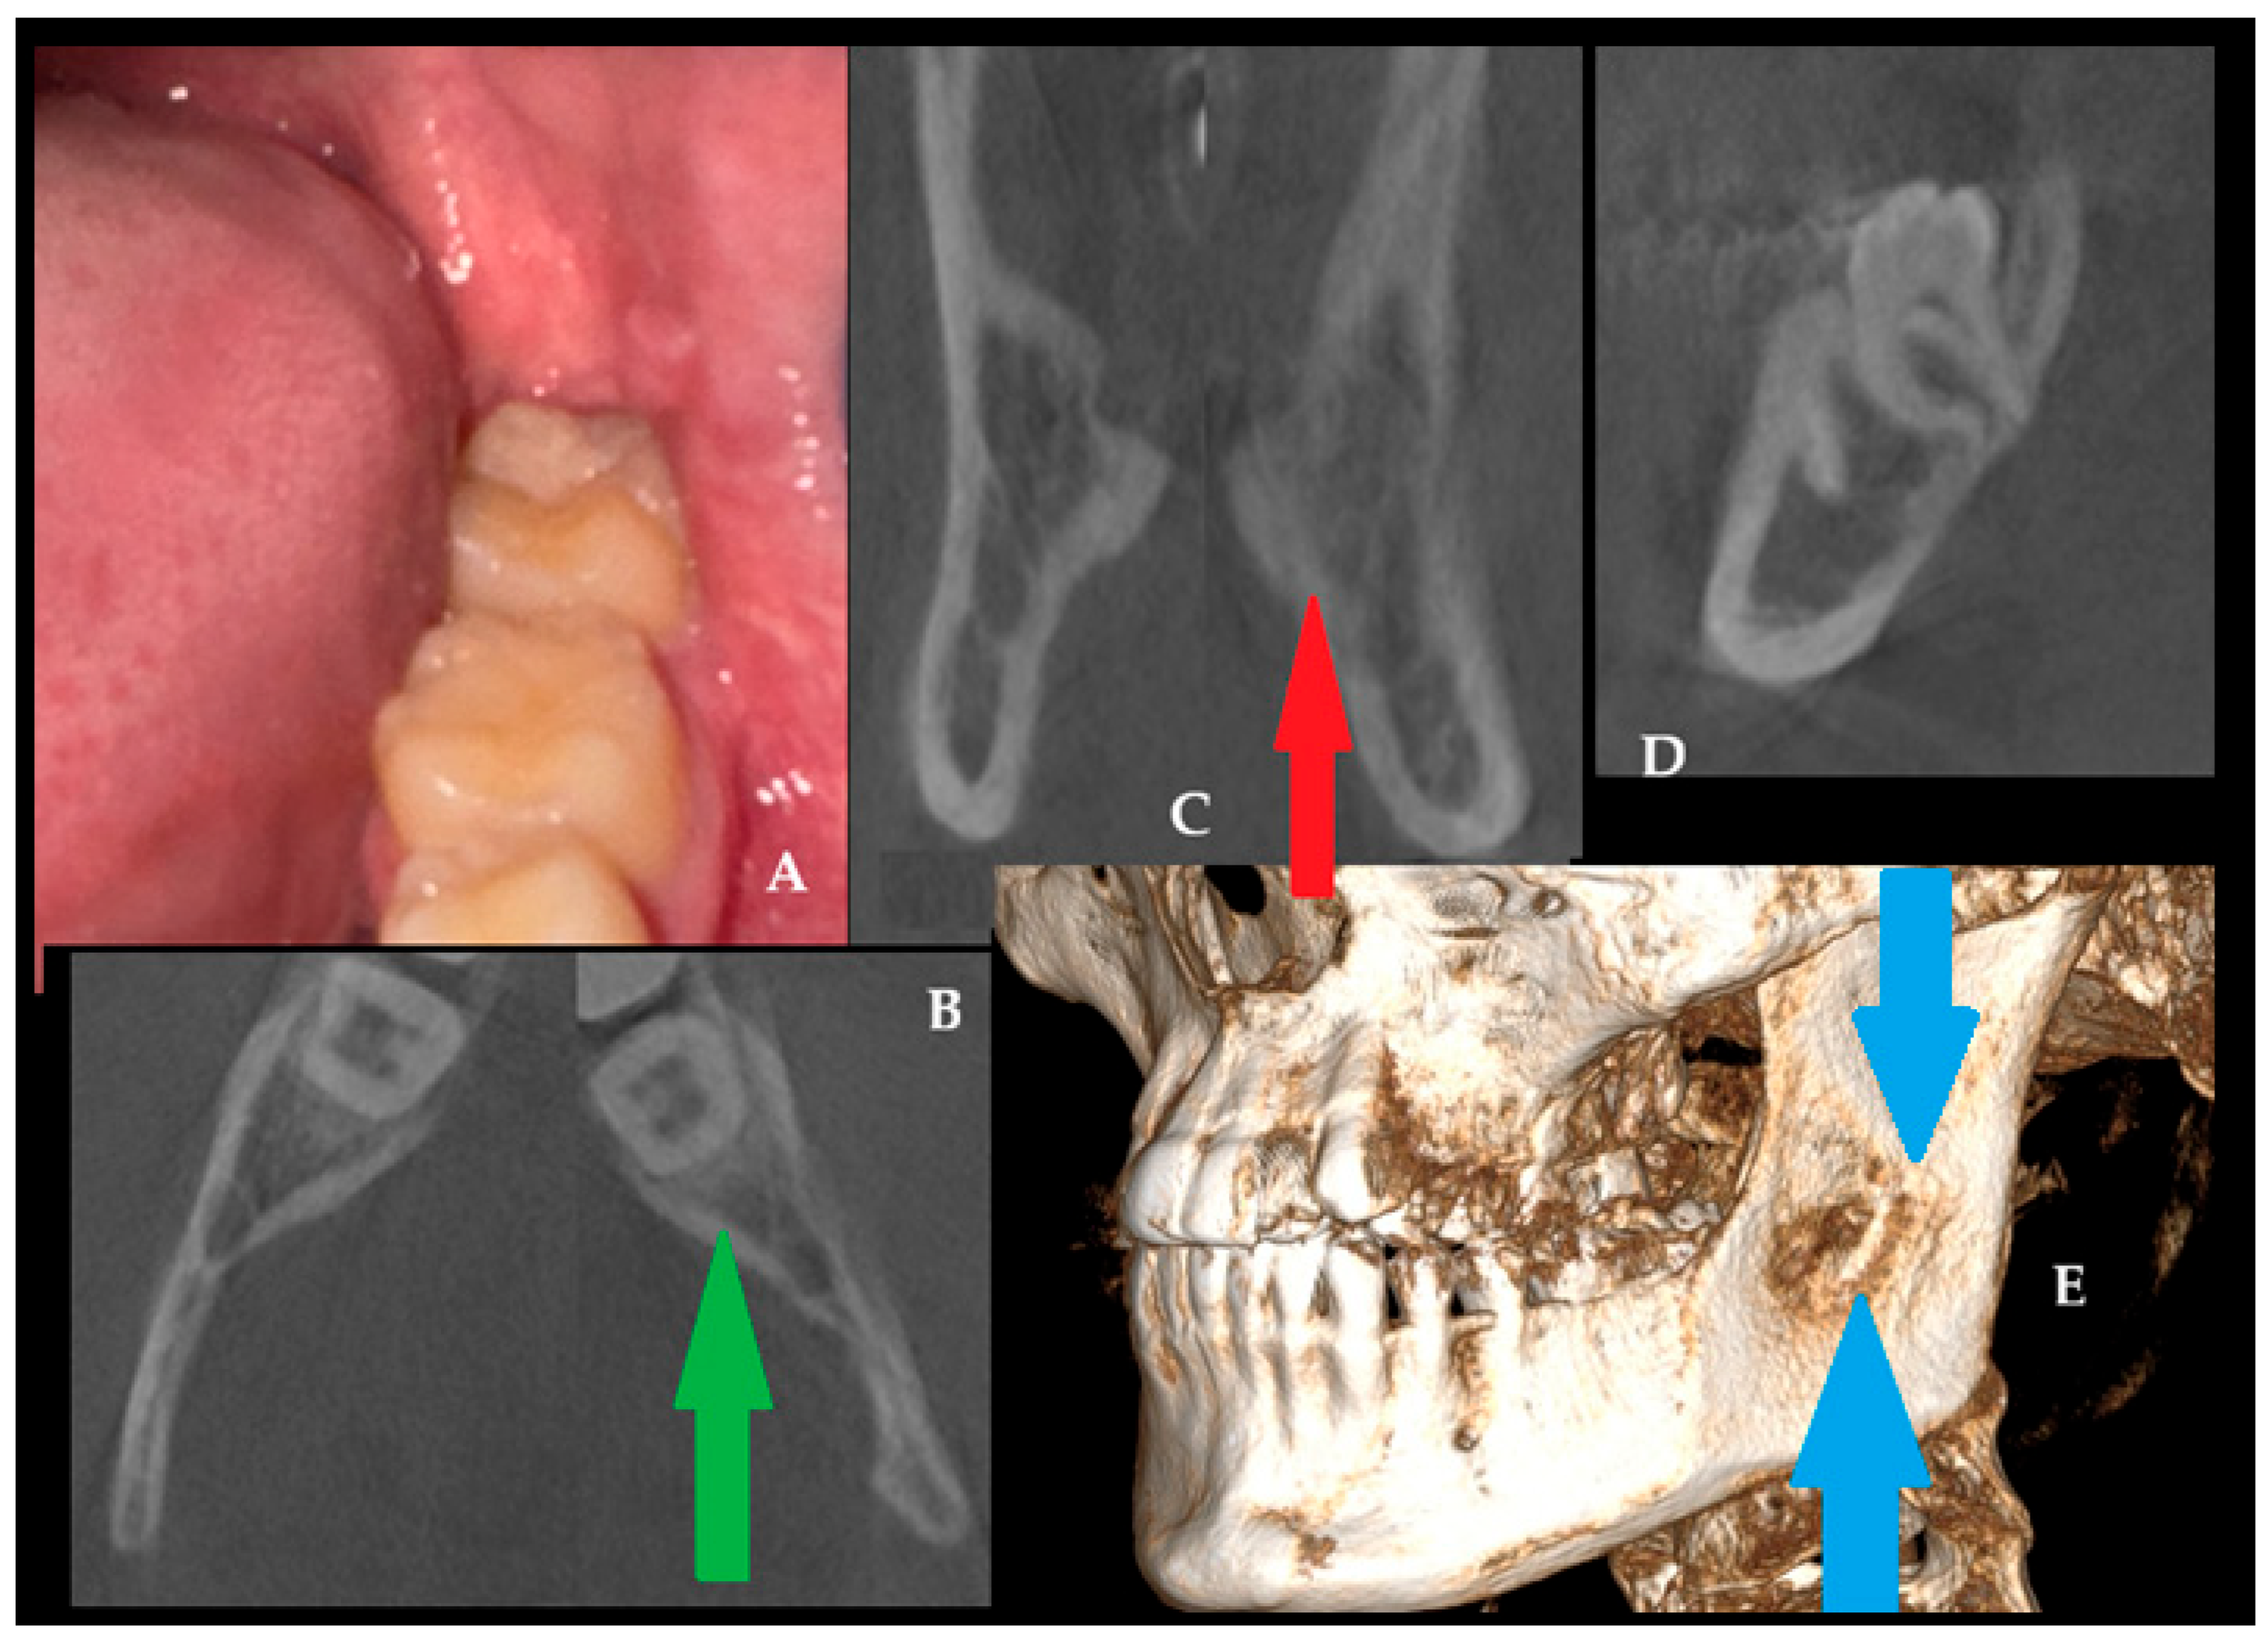

Postoperative MR (magnetic resonance) (A) with CBCT (B) after 12 months was used to evaluate the bone and adjacent soft tissue structure (Figure 6A). A satisfactory surgical outcome was achieved, with no radiographic evidence of recurrence or additional bone involvement. After surgery, a combination of MR-CBCT and MR-CT evaluations every six months for a year was conducted, and then, they were conducted once a year. This step was quite important for early detection of any relapse or secondary manifestation of OMs. The green arrows in Figure 6B indicate satisfactory bone healing, with comparable bone structures on both sides of the retromolar mandible. This surgical approach, consisting of biopsy combined with burr osteotomy, achieved a favorable outcome. This case underlines how OPG evaluation could be related to the early stages of this odontogenic tumor occurrence and its resemblance to an FC, growth patterns, and early detection during orthodontic screening. The intraoral approach did not reveal any worrisome findings in the patient.

In this case (Figure 7), a favorable clinical (A) and radiological outcome was observed during the 24-month follow-up period. In a control CBCT axial view (green arrow, B), the bone healed without any asymmetry or swelling (red arrow, B). On the other hand, the previously reported asymmetry, swelling, and extracortical spread (Figure 4A) are not present, and the bone is totally healed with proper bone structure (Figure 7C, coronal view). The sagittal CBCT view (D) with CBCT-3D bone reconstruction (blue arrows, E) reveals the presence of cortical bone loss after a radical ostectomy of surgical bone margins, with clearly visible healing observed without any worrisome symptoms. This locally aggressive lesion requires good surgical planning and, later, a careful clinical and radiological evaluation of each patient during follow-up. The scope of each surgery should be focused on each case individually. CBCT helps identify and monitor patients closely. This case highlights how excisional biopsy, together with OPG findings refined by CBCT, facilitated accurate evaluations of the odontogenic myxoma [11]. The patient is still under observation, and routine follow-ups are scheduled every six months.

Figure 6. Postoperative magnetic resonance ((A), sagittal view) and CBCT (B) were conducted to assess bone healing. Green arrows ((B), axial view) point to good bone healing and proper bone structure after the procedure.

Figure 7. Healing results after a 24-month time frame (A,B). Bone swelling has disappeared ((C), red arrow), while the bone structure behind the second mandibular left molar is well restored (B,D), green arrow). Three-dimensional CBCT evaluation (blue arrows) demonstrates satisfactory bone healing and restoration of normal bone structure (E).